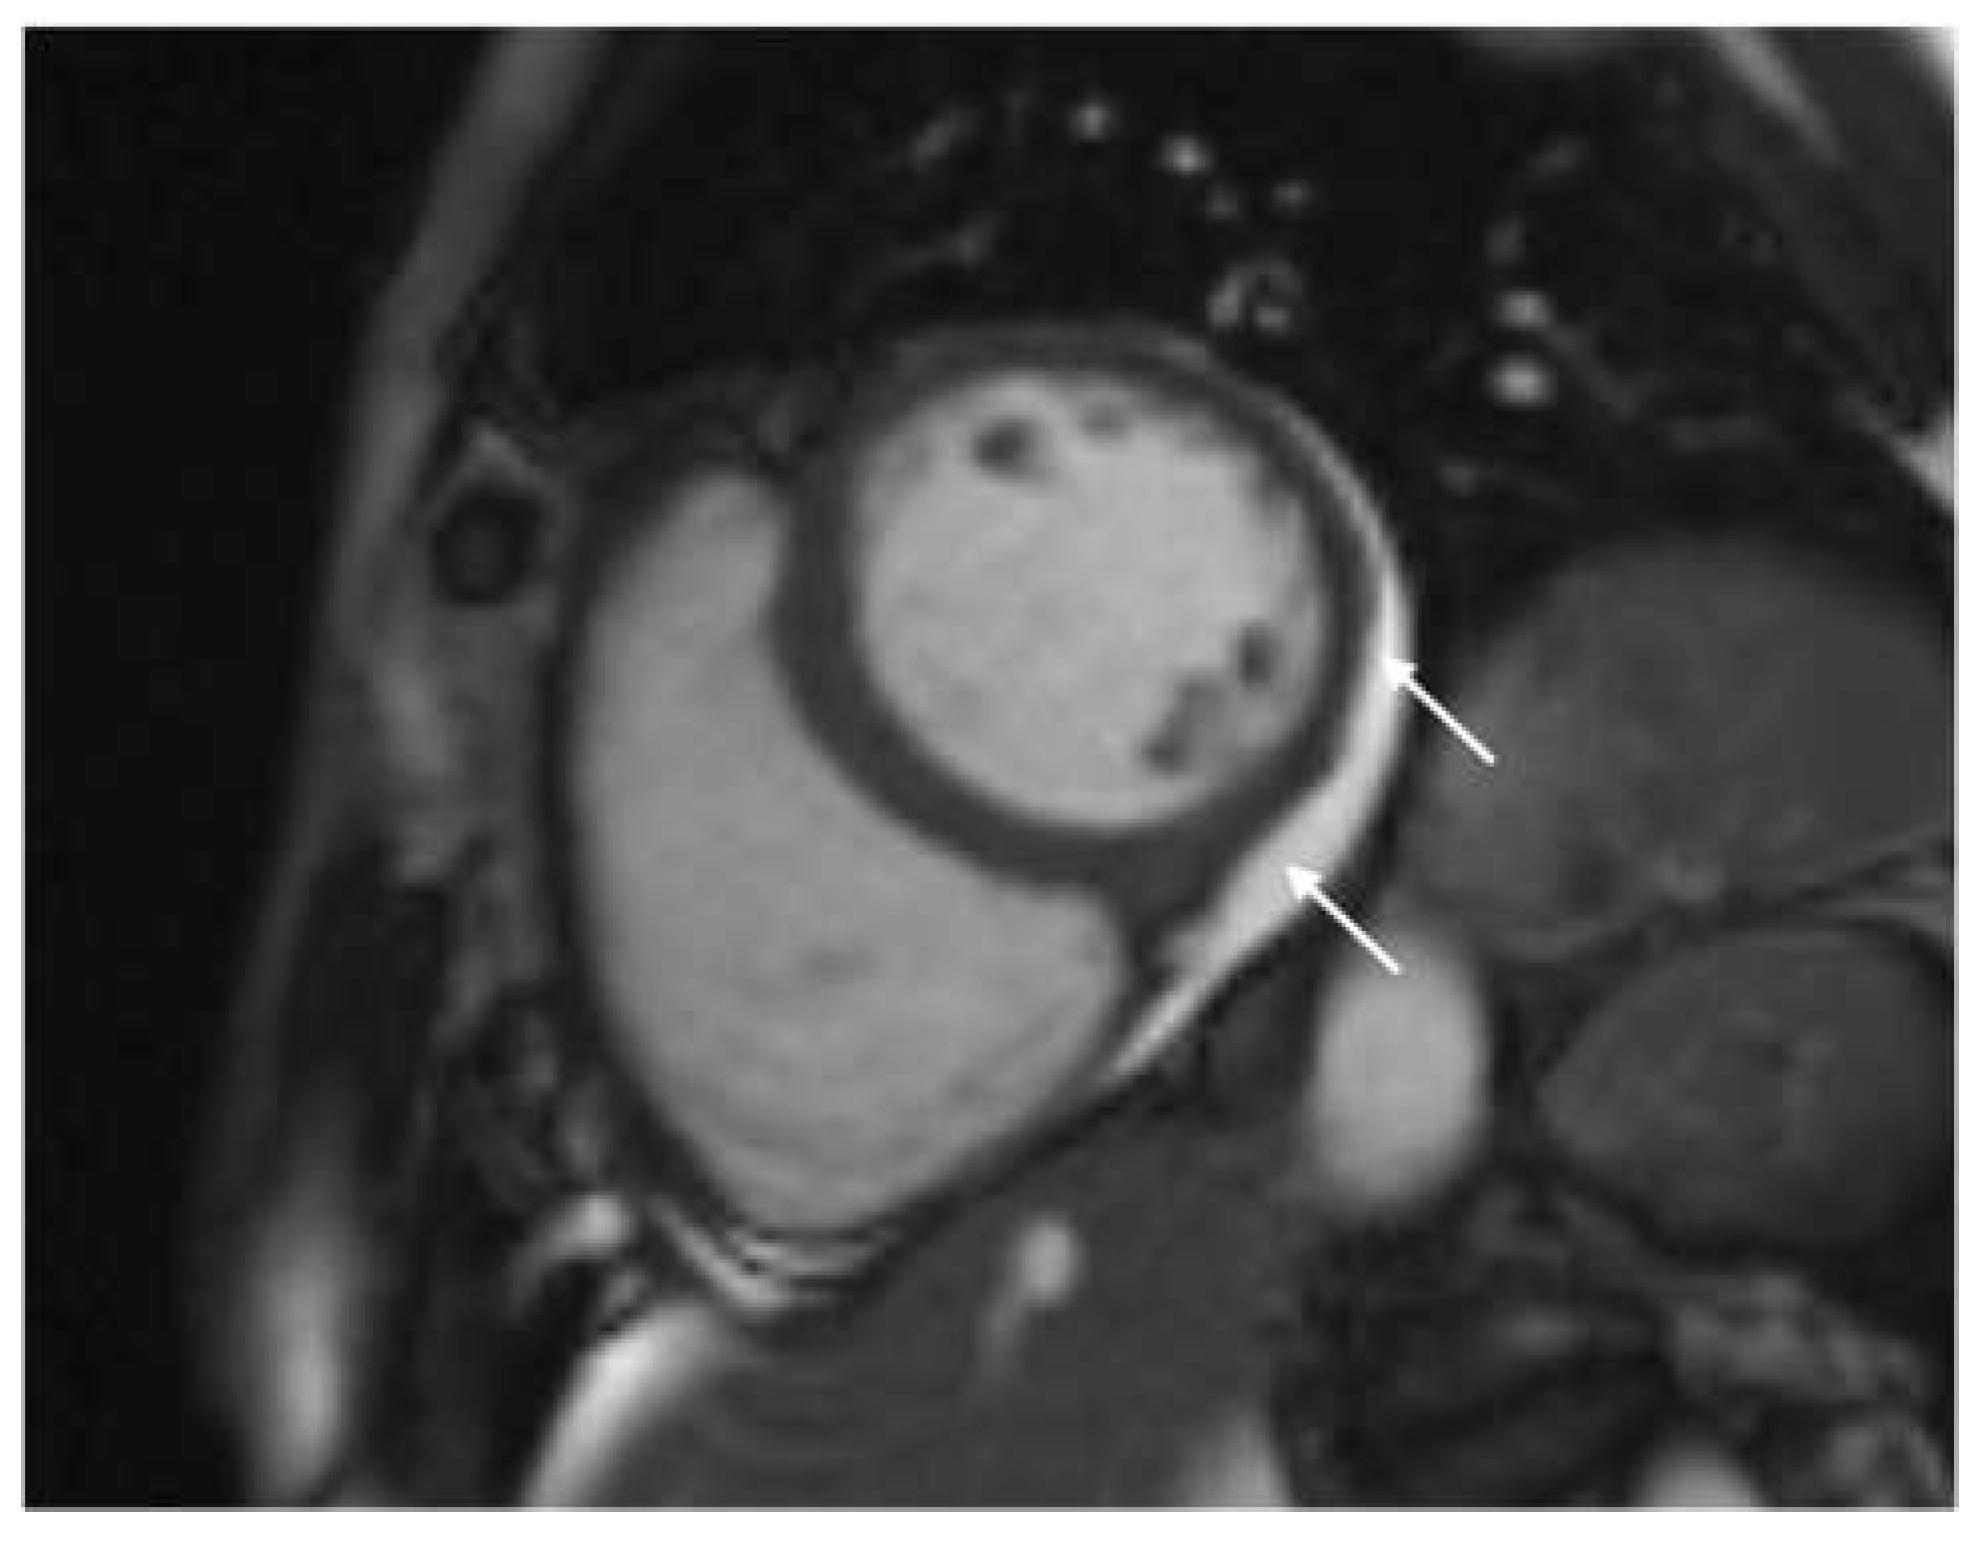

In our study, the majority of patients undergoing CMR examination had LGE in a non-ischemic distribution pattern. Specifically, LGE was predominantly localized in the inferolateral segments, particularly at the base and mid of the left ventricle (LV), with a subepicardial and/or mid-wall distribution (Figure 3). This pattern aligns with findings from studies on patients with other forms of viral myocarditis [1]. LGE is indicative of tissue inflammation, necrosis, and fibrosis, suggesting that myocarditis is a primary mechanism of direct myocardial injury caused by COVID-19 [35,36]. The simultaneous presence of LGE and edema points to active inflammation, and at this stage, LGE may not indicate definitive damage, as it often resolves upon follow-up [18,37]. Conversely, studies have shown that LGE without accompanying edema on a 6-month follow-up CMR is indicative of definitive fibrosis, representing irreversible myocardial injury [18,38,39]. Additionally, earlier studies on other types of viral myocarditis have demonstrated that LGE carries prognostic significance, often correlating with a worse prognosis [18,40].

Figure 3.

(a) Phase-sensitive inversion recovery (PSIR), mid-ventricular short axis slice: subepicardial and mid-wall (non-ischemic) distribution of late gadolinium enhancement (LGE) in the mid inferolateral segment (marked with arrows); (b) phase-sensitive inversion recovery (PSIR) long axis (four chamber): subepicardial and mid-wall (non-ischemic) distribution of late gadolinium enhancement (LGE) in the mid lateral segment (marked with arrows). This pattern of LGE indicates post-inflammatory fibrosis.